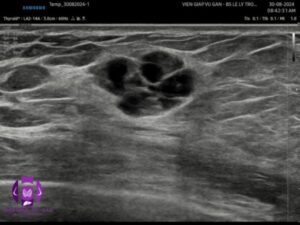

- Vú phải: vị trí 10g rìa vú có echo hỗn hợp dạng đặc và nang, bờ đa cung lớn, giới hạn rõ, không vôi, tăng âm phía sau, kích thước 20x12x10mm . Doppler: mạch máu phân bố thưa thớt ở ngoại vi

- Kết luận: Tổn thương vú phải( BI-RADS 3)

- Trên siêu âm, bọc sữa thường là khối u nang (cystic mass) có tăng âm phía sau, độ hồi âm phụ thuộc vào hàm lượng thành phần bên trong (chất béo, đạm, nước). Không bao giờ xuất hiện mạch máu bên trong. (2,3)